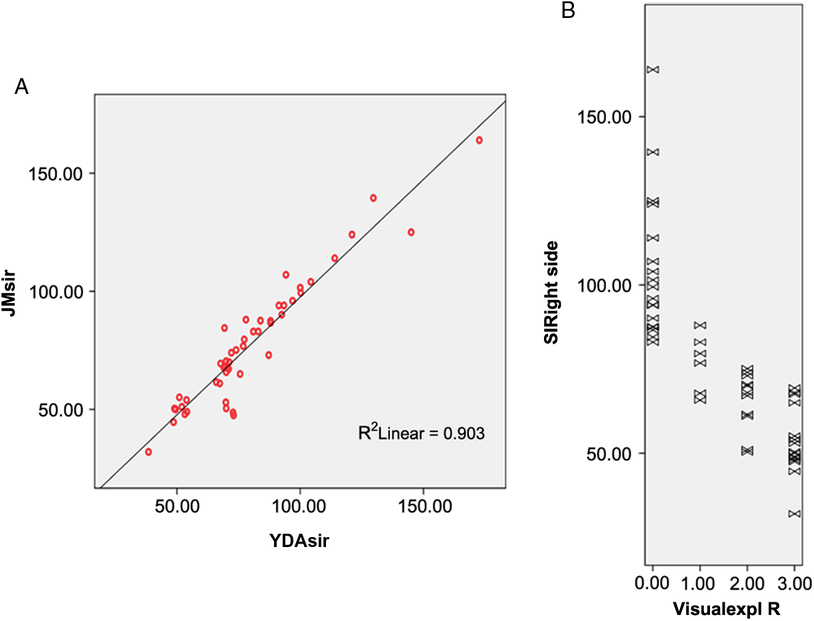

Figure 1: (A) Inter-rater reproducibility of signal intensity measurements in the region of interest performed by two physicians at separate institutions. Pearson’s coefficient is 0.95 (p < 0.001). (B) Relationship between visual interpretation of the black ribbon rated on a 4-point scale and signal intensity in arbitrary units (r = −0.818, p < 0.001).

Validation Process

Twenty-nine patients with definite ALS (80.55%) exhibited a ribbon of reduced signal intensity in the posterior tier of both precentral gyri and four patients (11%) exhibited the sign unilaterally, contralateral to the affected arm. The visual observer analysis had a intra-rater and inter-rater concordance of 0.98 and 0.97, respectively, after the training period, indicating excellent consistency. Signal intensity of the BR was also significantly correlated with the ordinal scale of visual interpretation with correlation coefficients of −0.770 for the left side and −0.833 for the right side (p < 0.001) (Figure 1B). Yet, there was not so good relationship between measured BR area and visual evaluation results (Spearman’s rho coefficient = 0.370, p = 0.04) for the right side and (0.432, p = 0.01) for the left side.

BR Sign Measurement